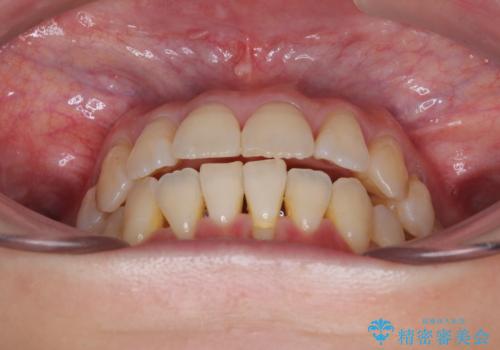

前歯のデコボコをインビザラインで目立たずに改善

- 上下前歯のデコボコを気にして来院された患者様です。

デコボコは顕著であるものの、口元の突出感は強くないため、非抜歯にて矯正治療を行うこととしました。

元々の叢生と歯肉退縮傾向になる歯肉であったため、ブラックトライアングルが目立つことが想定されました。

治療過程でブラックトライアングル改善のため、IPR(歯と歯の間を削る)を活用しました。